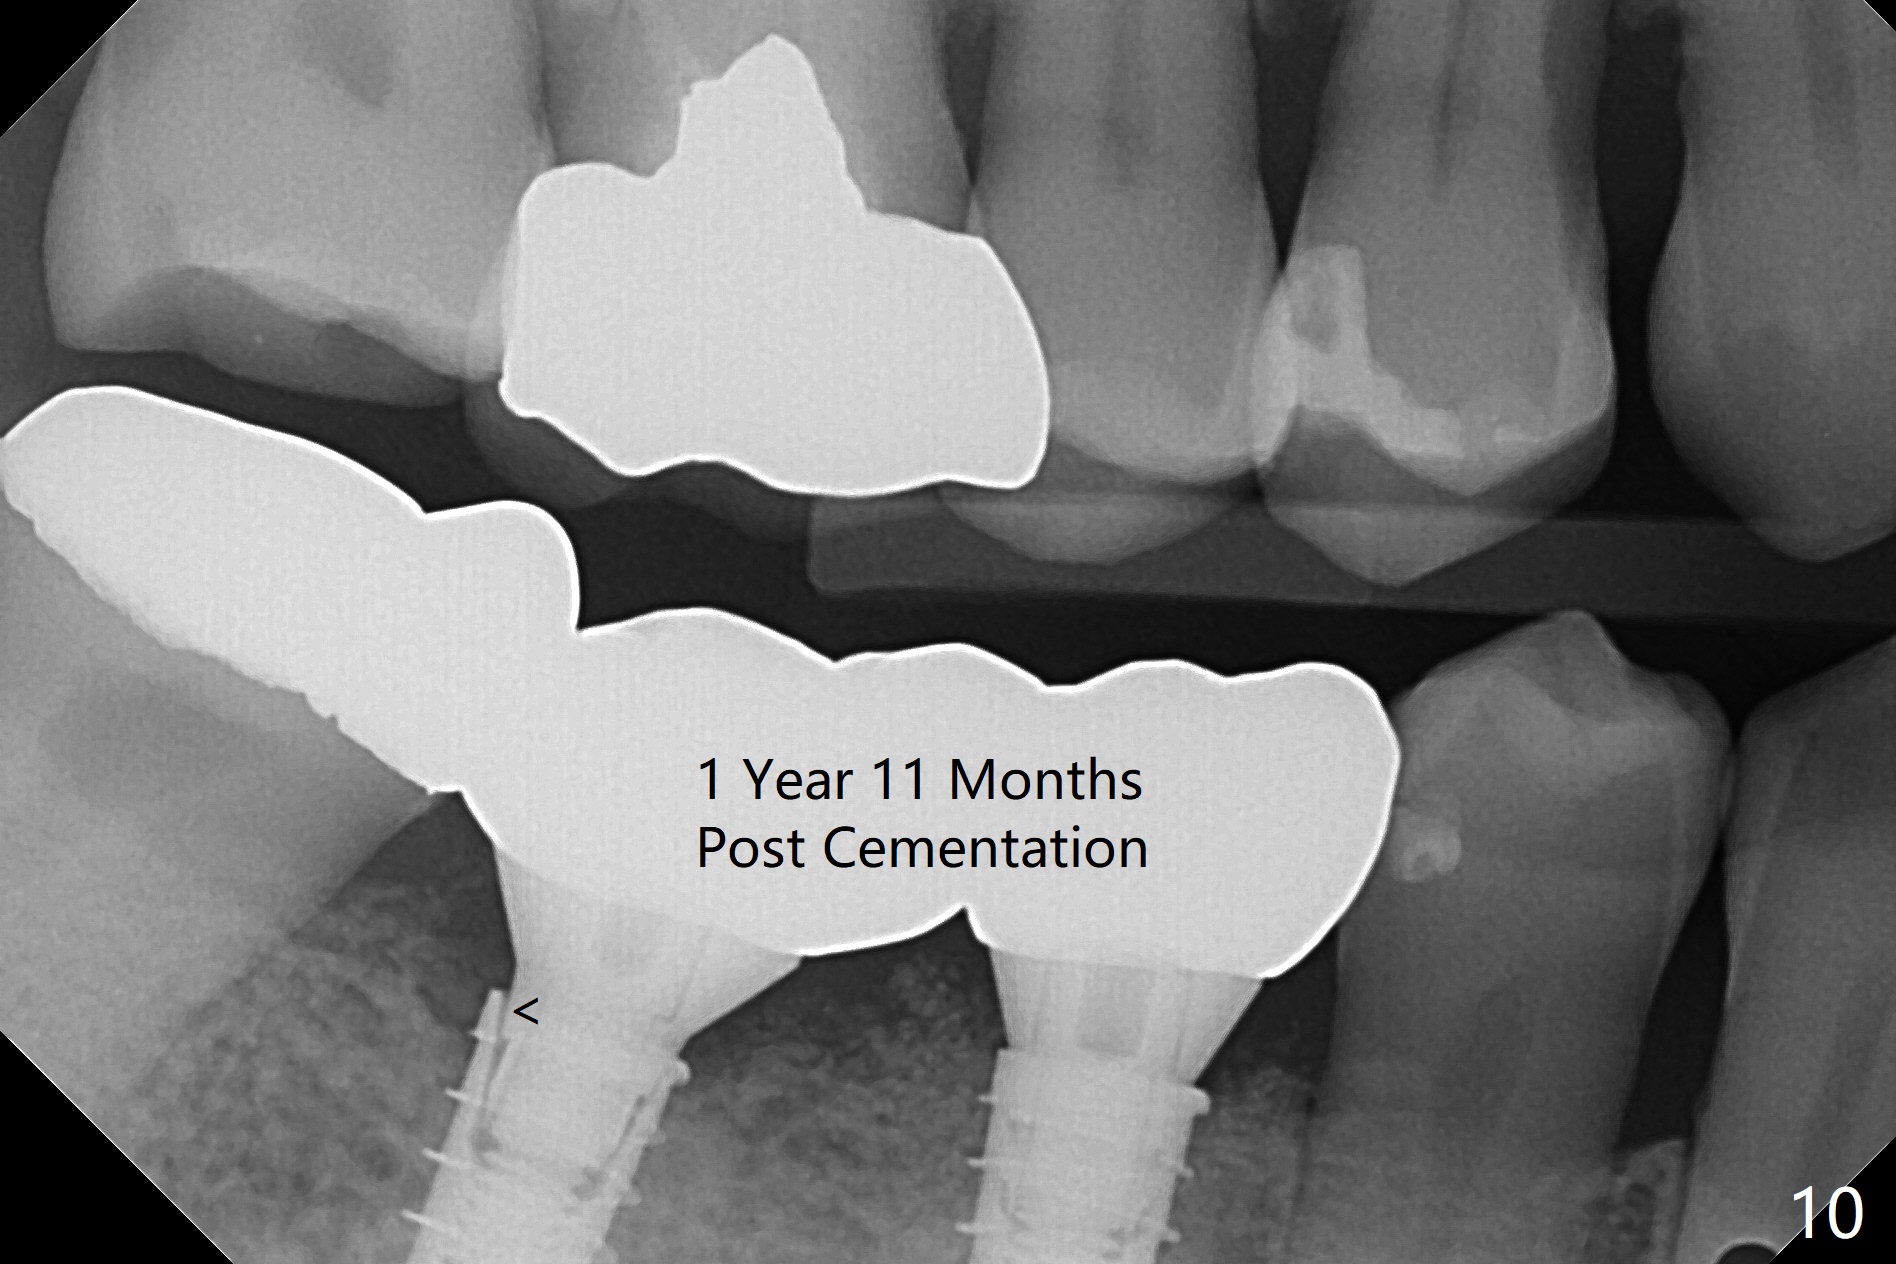

After incision, the ridge at #29 and 30 is found ~ 5 mm wide buccolingually. To place a 4x11 mm IBS implant at #30, the ridge is expanded using BEB technique (bone expansion and bending, Fig.1). It appears that the initial osteotomy at #29 is mesial (Fig.1 yellow dashed line: the distal surface of the root of the tooth #28). After moving the osteotomy distal, the final implant position at #29 (4x11 mm) is within normal limit (Fig.2). The bone at #29 seems to be not so dense that bending (using 1.6 mm drill) is not necessary (using Magic Split and Magic Expanders 3 and 3.8 mm). Later the implant at #30 (4x11 mm) is placed deeper (Fig.3). After placing bone graft around the implants/abutments and suturing, the ridge looks wider with apparent formation of the gingival bands around the abutments (Fig.4 *). Three months and a half postop, bone loss is minimal (Fig.5) and gingival bands forms around the abutments (Fig.6). Fig.7 is taken 1 month post cementation (panoramic X-ray). The patient chews normally 1 year (Fig.8) and nearly 2 years (Fig.9,10) post cementation. The crown at #31 needs recementation 2 years 7 months post #30 cementation; the incomplete seating of the abutment was noted for the first time (Fig.11). Five months later the patient is going to be retired and wants to travel abroad. After approval, the access hole was reopened; articulating paper shows under occlusion of the crown (Fig.12). Since the gap between the abutment and the implant is large, the abutment/crown complex seems to be necessary to be turned (Fig.13 curved arrow). The proximal surfaces of the crown need to be trimmed (straight lines). After turning, the crown sits down with screw tightening; the patient feels pain from the gingival cuff (Fig.14). After turning, the abutment appears to be completely seated (Fig.15). In fact the mesial and distal surfaces of the crown should have clearance from the neighboring teeth (Fig.14) so that pick-up impression is able to hold the crown/abutment complex securely (Fig.16: *). The crown is separated from the abutment after crown repair. They are seated together (loose connection) using the crown as a guide to seat the abutment. BW is taken without the crown. It appears that the abutment remains seated completely (Fig.17). The apical space is equal between #29 and 30 (Fig.17, as compared to Fig.5).